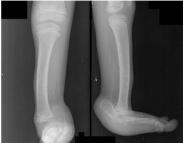

先天性肌缺如(congenital absence of muscles)臨床上比較少見(jiàn),是由于胎兒本身發(fā)育異常,或因在宮內(nèi)受到機(jī)械阻礙所致。常表現(xiàn)為單塊肌肉部分或全部缺如,也可表現(xiàn)為某一組肌肉的缺如。如果缺如的肌肉不能被其他正常肌肉所代償,則可能出現(xiàn)畸形。